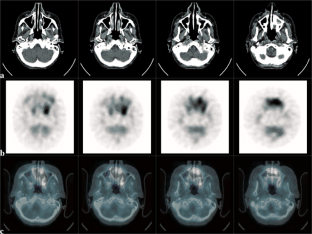

Abb. 4 a–c: